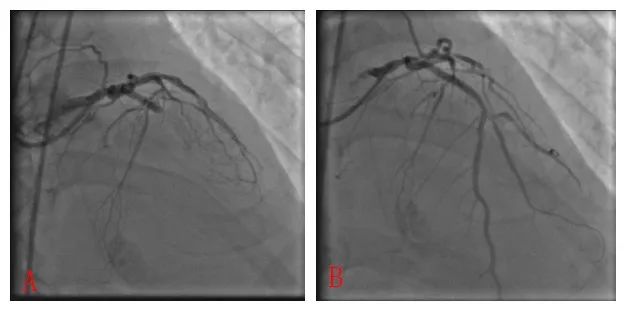

图1:A 2009年1月1日,术前ST段抬高;B 术后ST段回落。

图2:A 2009年1月1日术前LAD闭塞;B 术后LAD通畅。